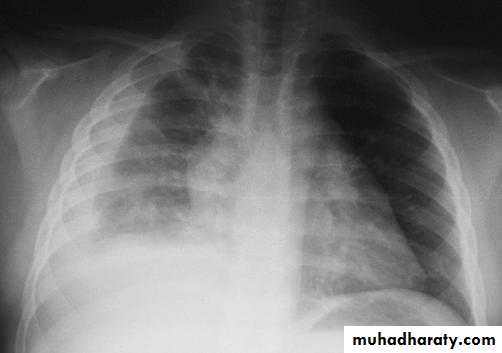

rt.upper lobe pn. Left lower lobe pn.